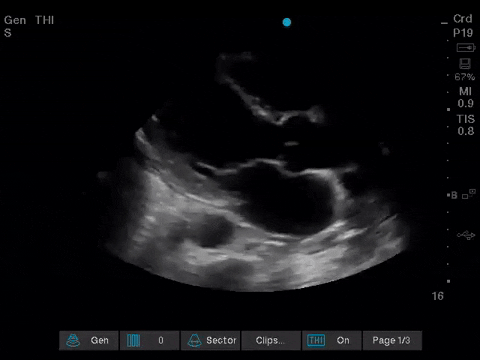

Before giving their clinical interpretation of the LUS findings, the POCUS team also scanned the heart and vasculature to obtain a more complete picture.

A comprehensive echocardiogram confirmed the POCUS findings. Her depressed LVEF was thought to be due to either septic cardiomyopathy or chemotherapy toxicity.